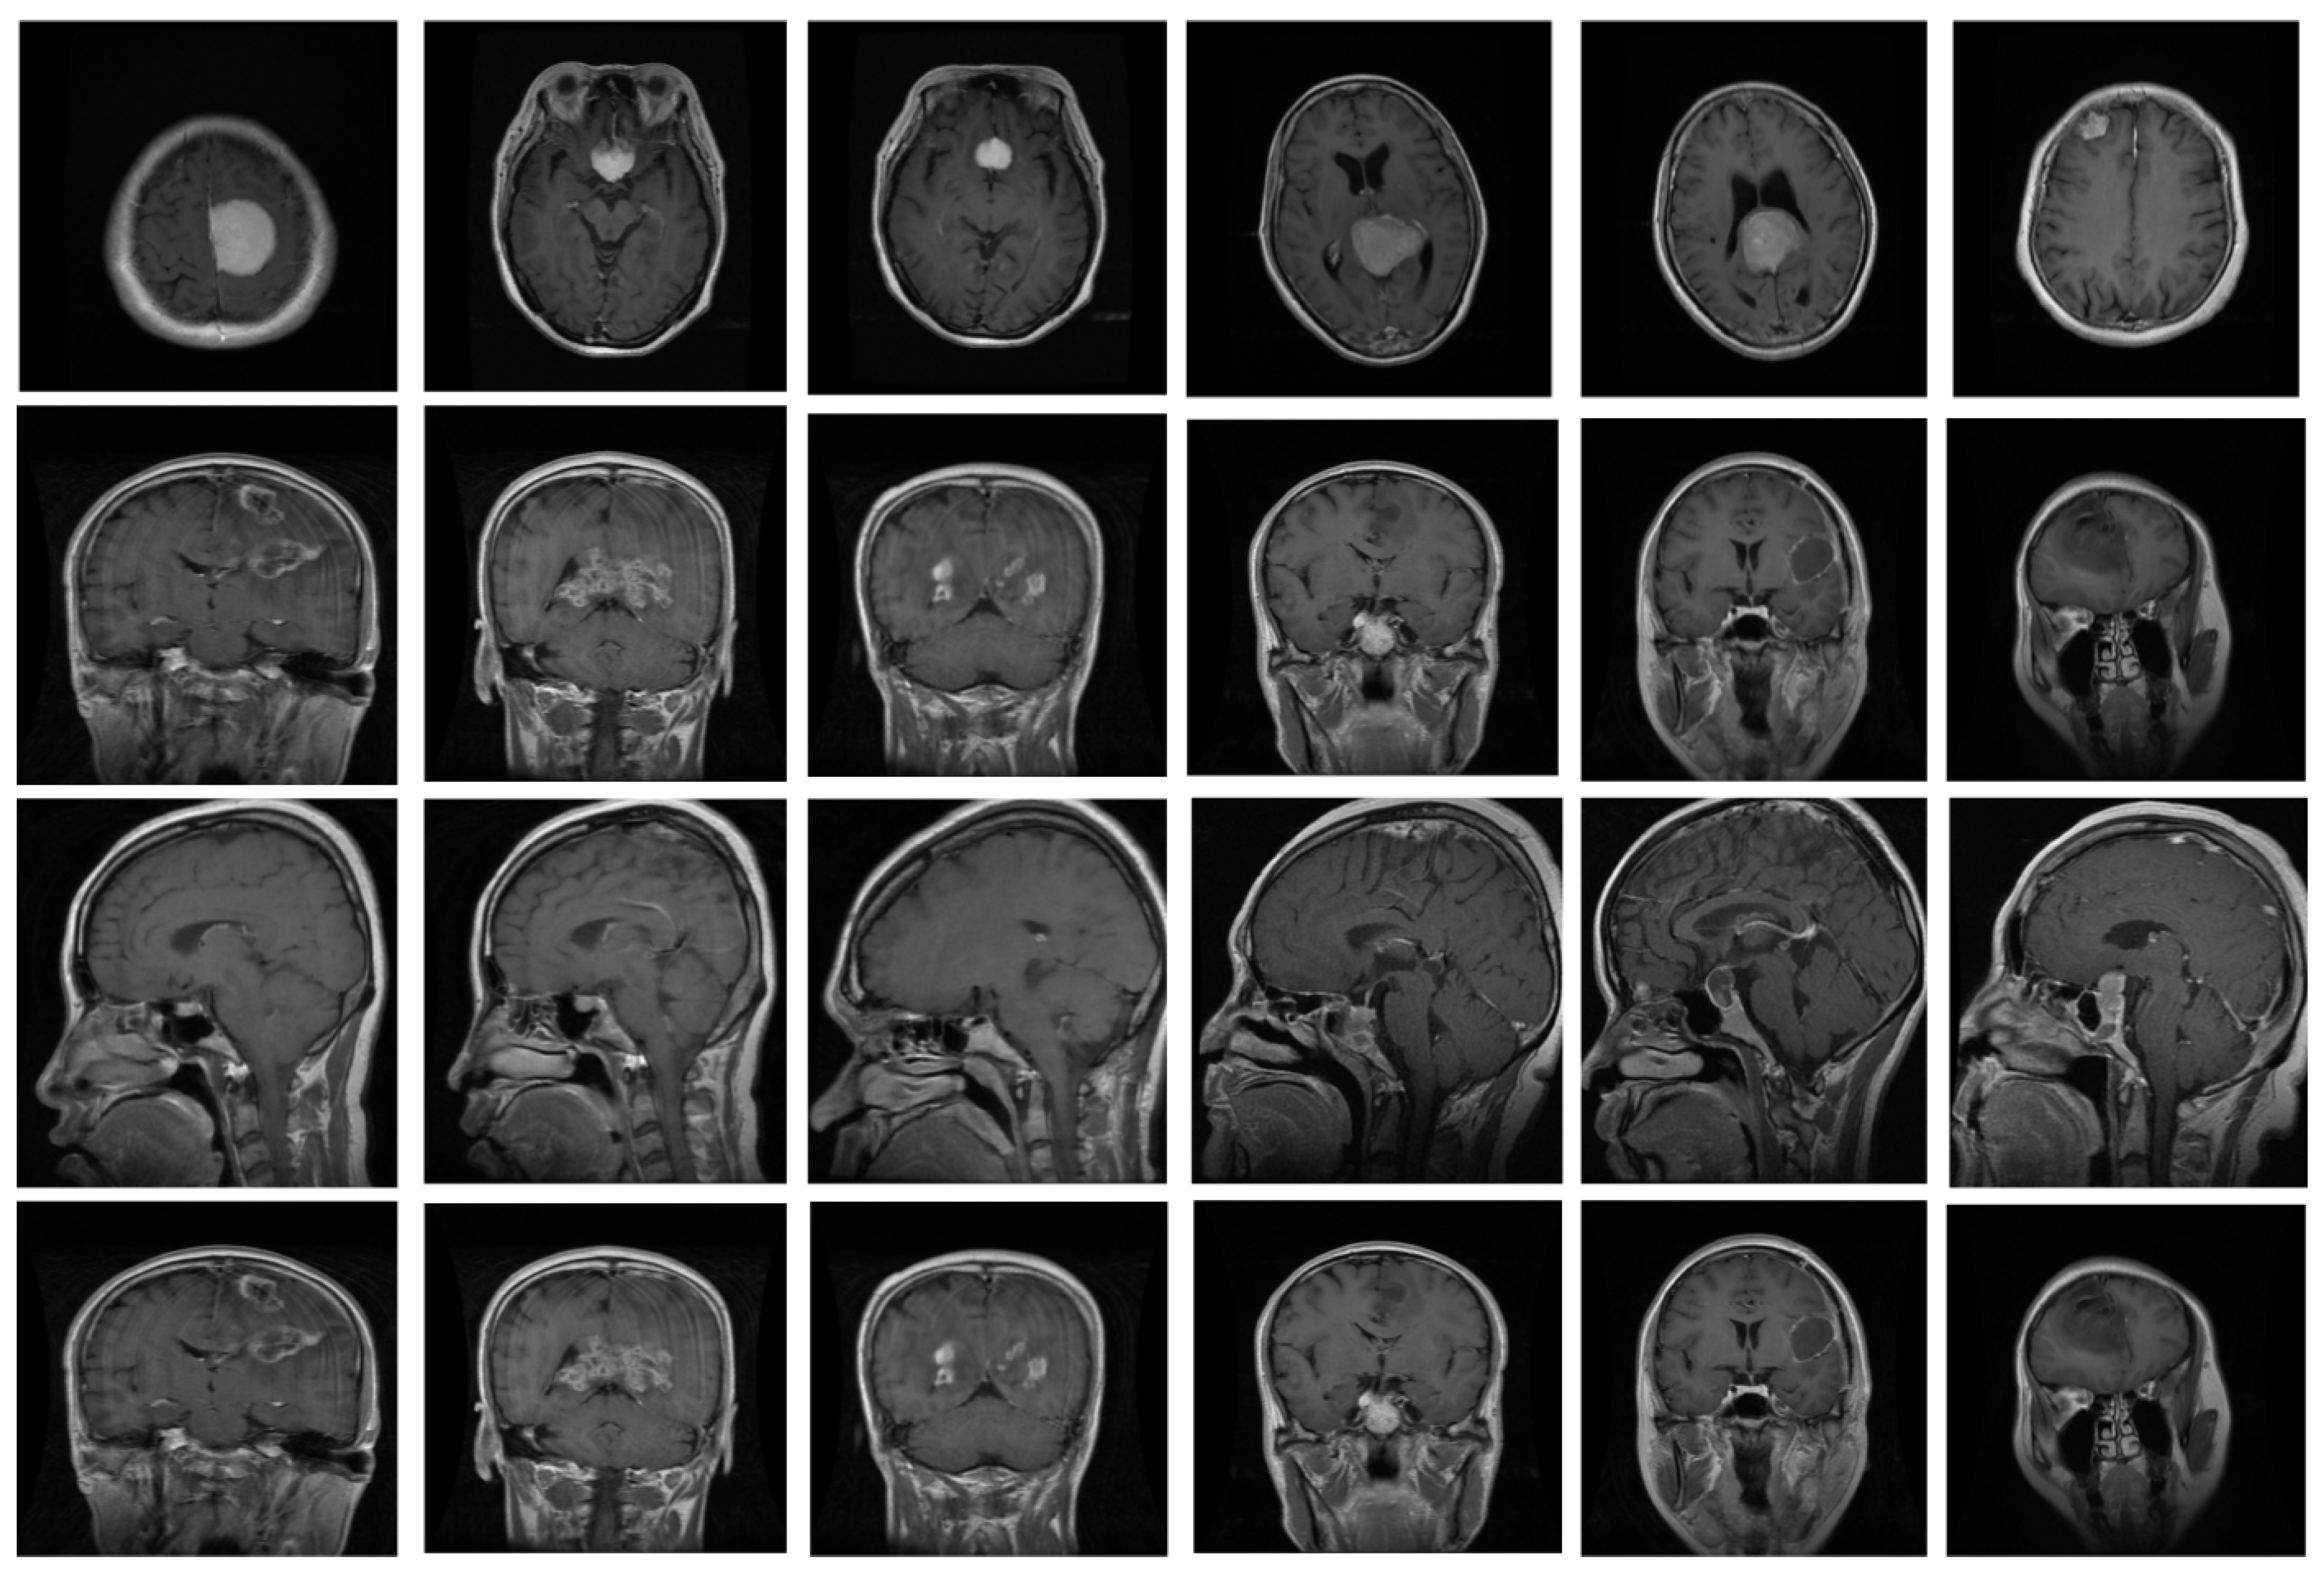

The proposed system underwent training and evaluation utilizing two distinct datasets: the Figshare dataset and Harvard medical images [31]. The Figshare dataset encompasses T1-weighted contrast-enhanced MRI images sourced from 233 individuals, yielding a total of 3064 brain images. This dataset consists of three categories of brain tumors, namely pituitary (930), glioma (1426), and meningioma (708), all of which were obtained from Nanfang hospital in China. The samples in this dataset measure 512 × 512 in size. On the other hand, the Harvard medical dataset was composed of ten tumors, as diagnosed by various experts. The brain MRIs in the Harvard dataset were captured in the axial plane, T2-weighted, and measured 256 × 256 pixels. We assessed the efficacy of our proposed detector using both datasets, but we only utilized the Figshare dataset for training purposes. Some sample images are depicted in Figure 4.

Figure 4. Some samples of brain MRI.